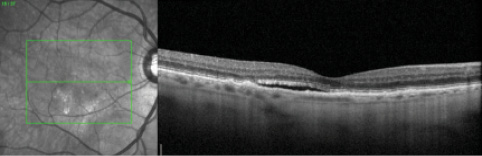

A 78-year-old man with a medical history of arterial hypertension, hypercholesterolemia, bicuspid aortic valve, deep vein thrombosis, and peripheral vascular disease had been undergoing therapy for neovascular AMD in the right eye (OD). On the day of an injection, ophthalmologic examination revealed best corrected visual acuity of 20/30 and intraocular pressure (IOP) of 14 mm Hg OD. Subretinal fluid was noted on clinical examination and confirmed with spectral-domain optical coherence tomography (SD-OCT) (Figure 1). The patient received an intravitreal injection of aflibercept with topical anesthesia.

Figure 1. OCT OD before injection of aflibercept reveals drusen and subretinal fluid.